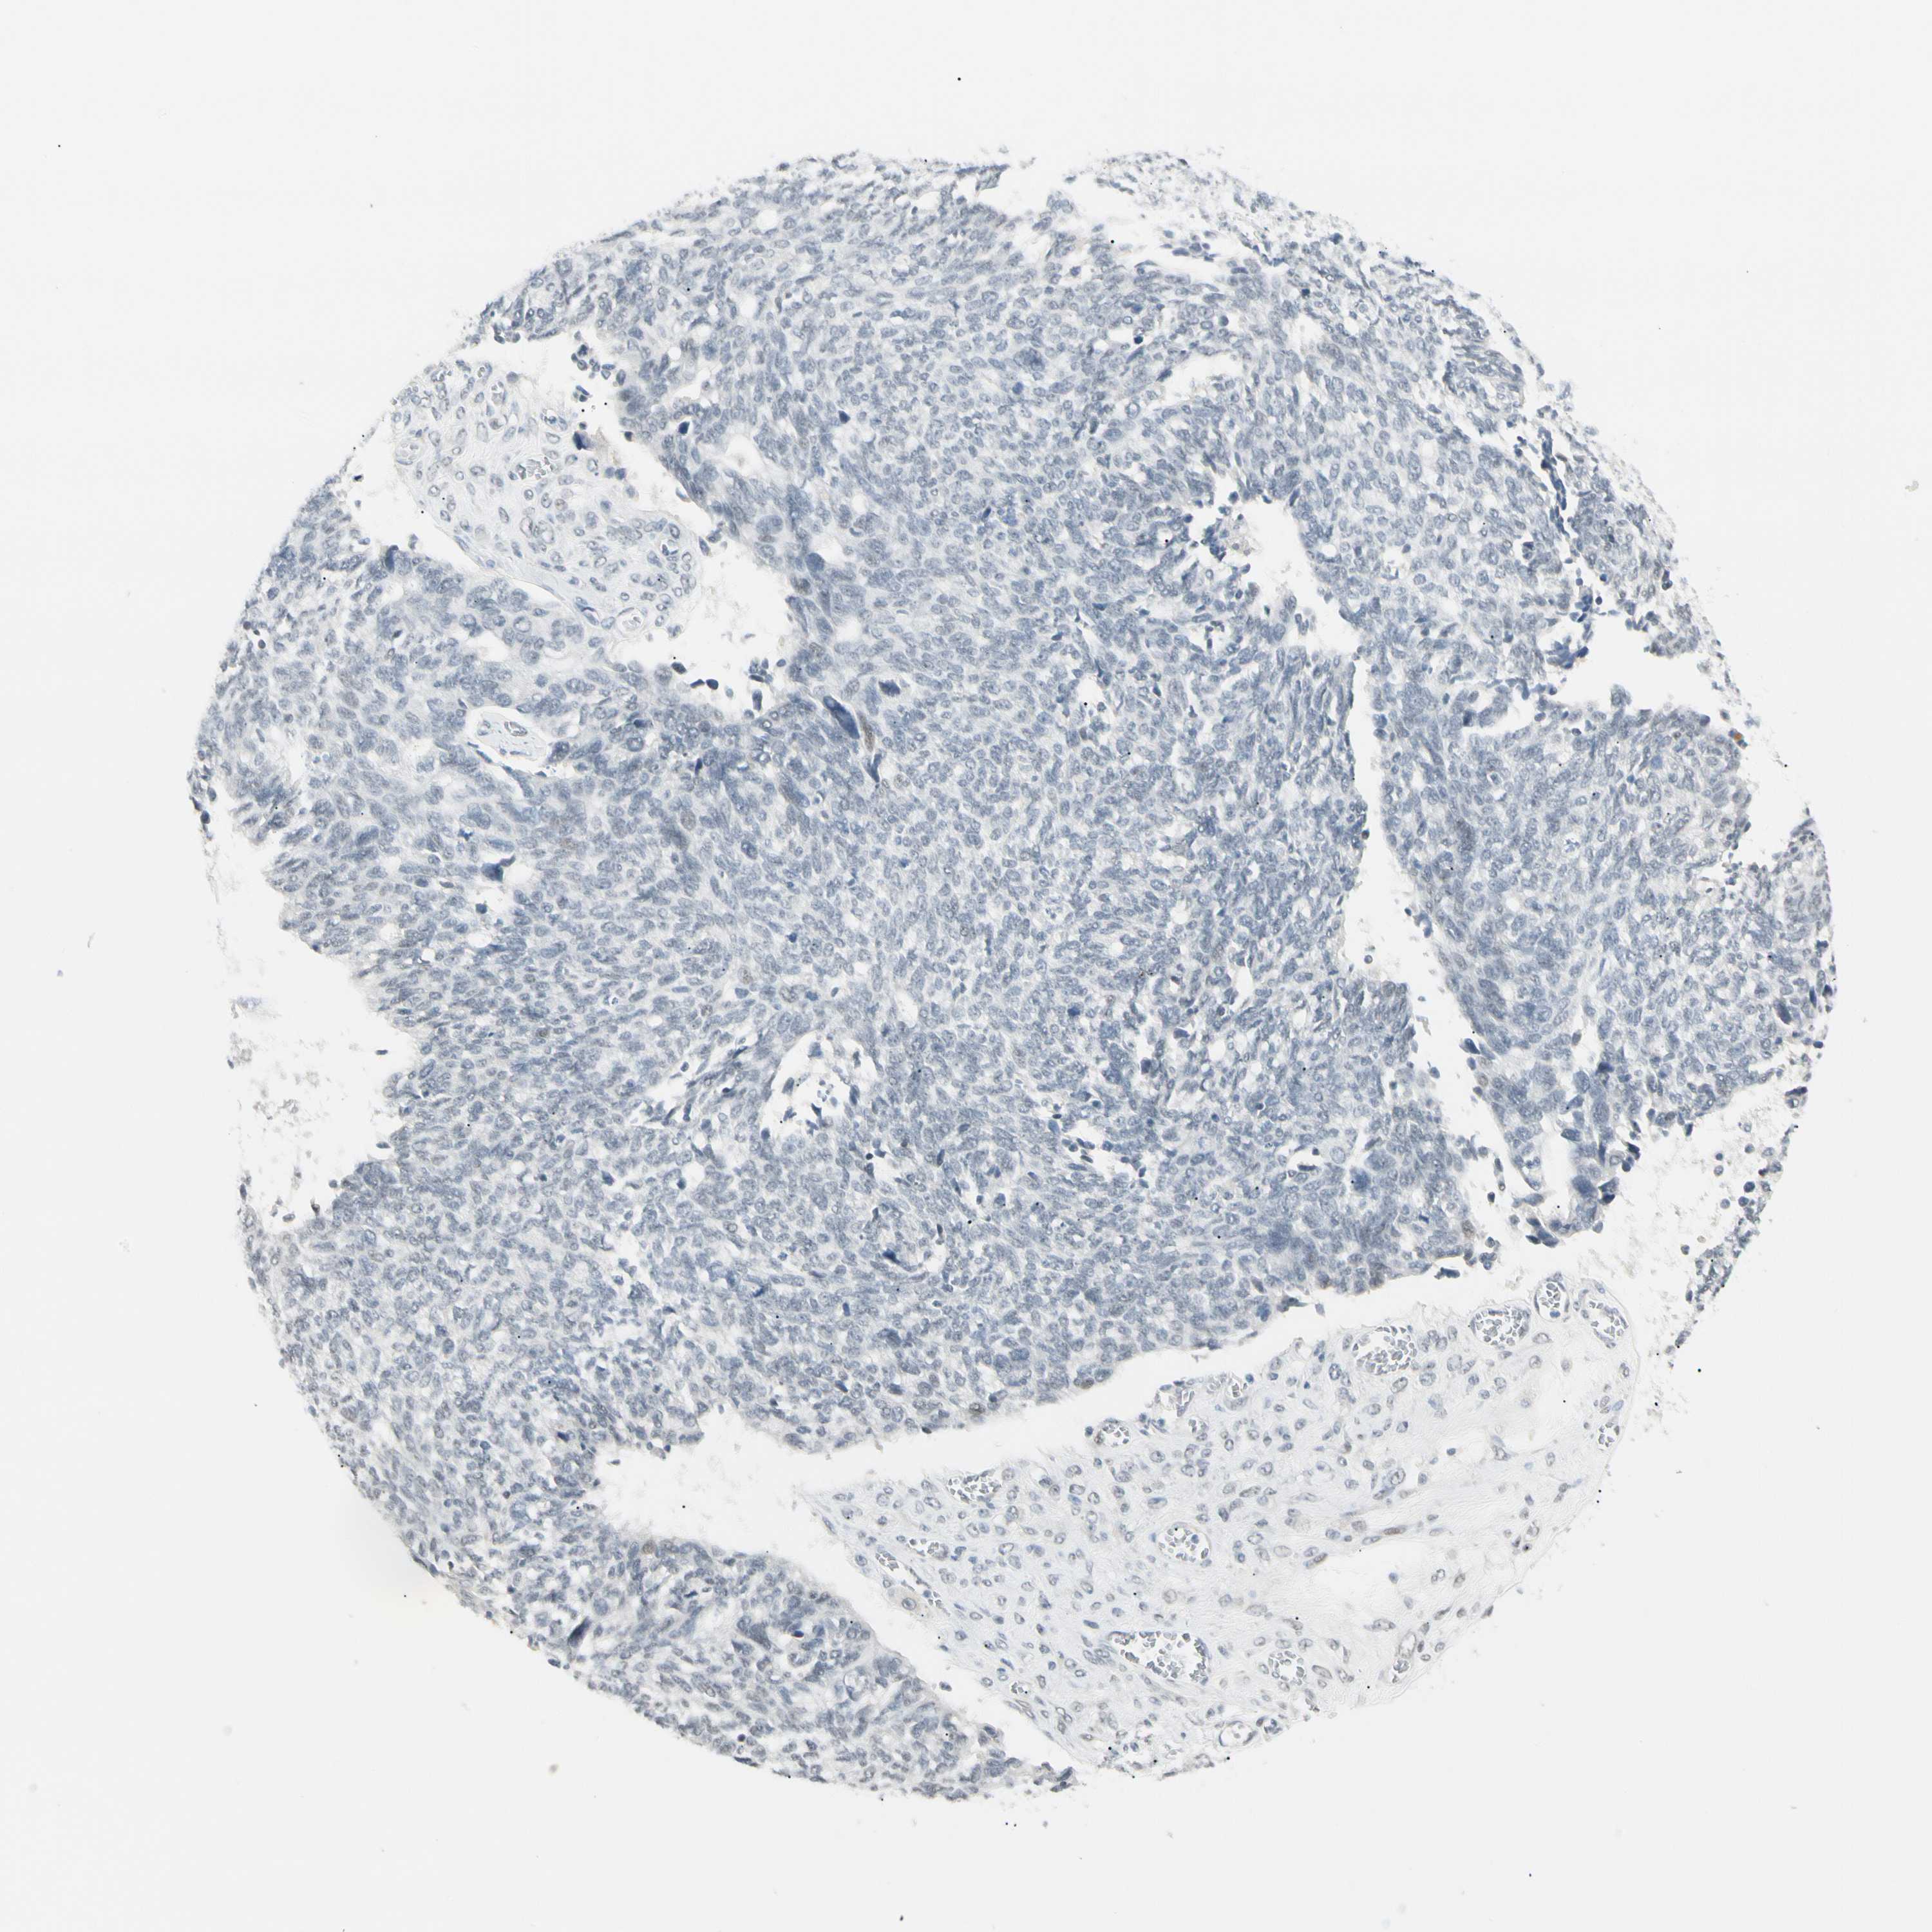

OVARIAN CANCER - Protein expressioni

A mouse-over function shows sample information and annotation data. Click on an image to view it in a full screen mode. Samples can be filtered based on level of antibody staining by selecting one or several of the following categories: high, medium, low and not detected. The assay and annotation is described here.

Note that samples used for immunohistochemistry by the Human Protein Atlas do not correspond to samples in the TCGA dataset.

Antibody stainingi

Antibody staining in the annotated cell types in the current human tissue is reported as not detected, low, medium, or high, based on conventional immunohistochemistry profiling in selected tissues. This score is based on the combination of the staining intensity and fraction of stained cells.

Each image is clickable and will lead to virtual microscopy that enables deeper exploration of all samples and also displays staining intensity scores, fraction scores and subcellular localization as well as patient and tissue information for each sample.

Antibody HPA008435

Cystadenocarcinoma, serous, NOS